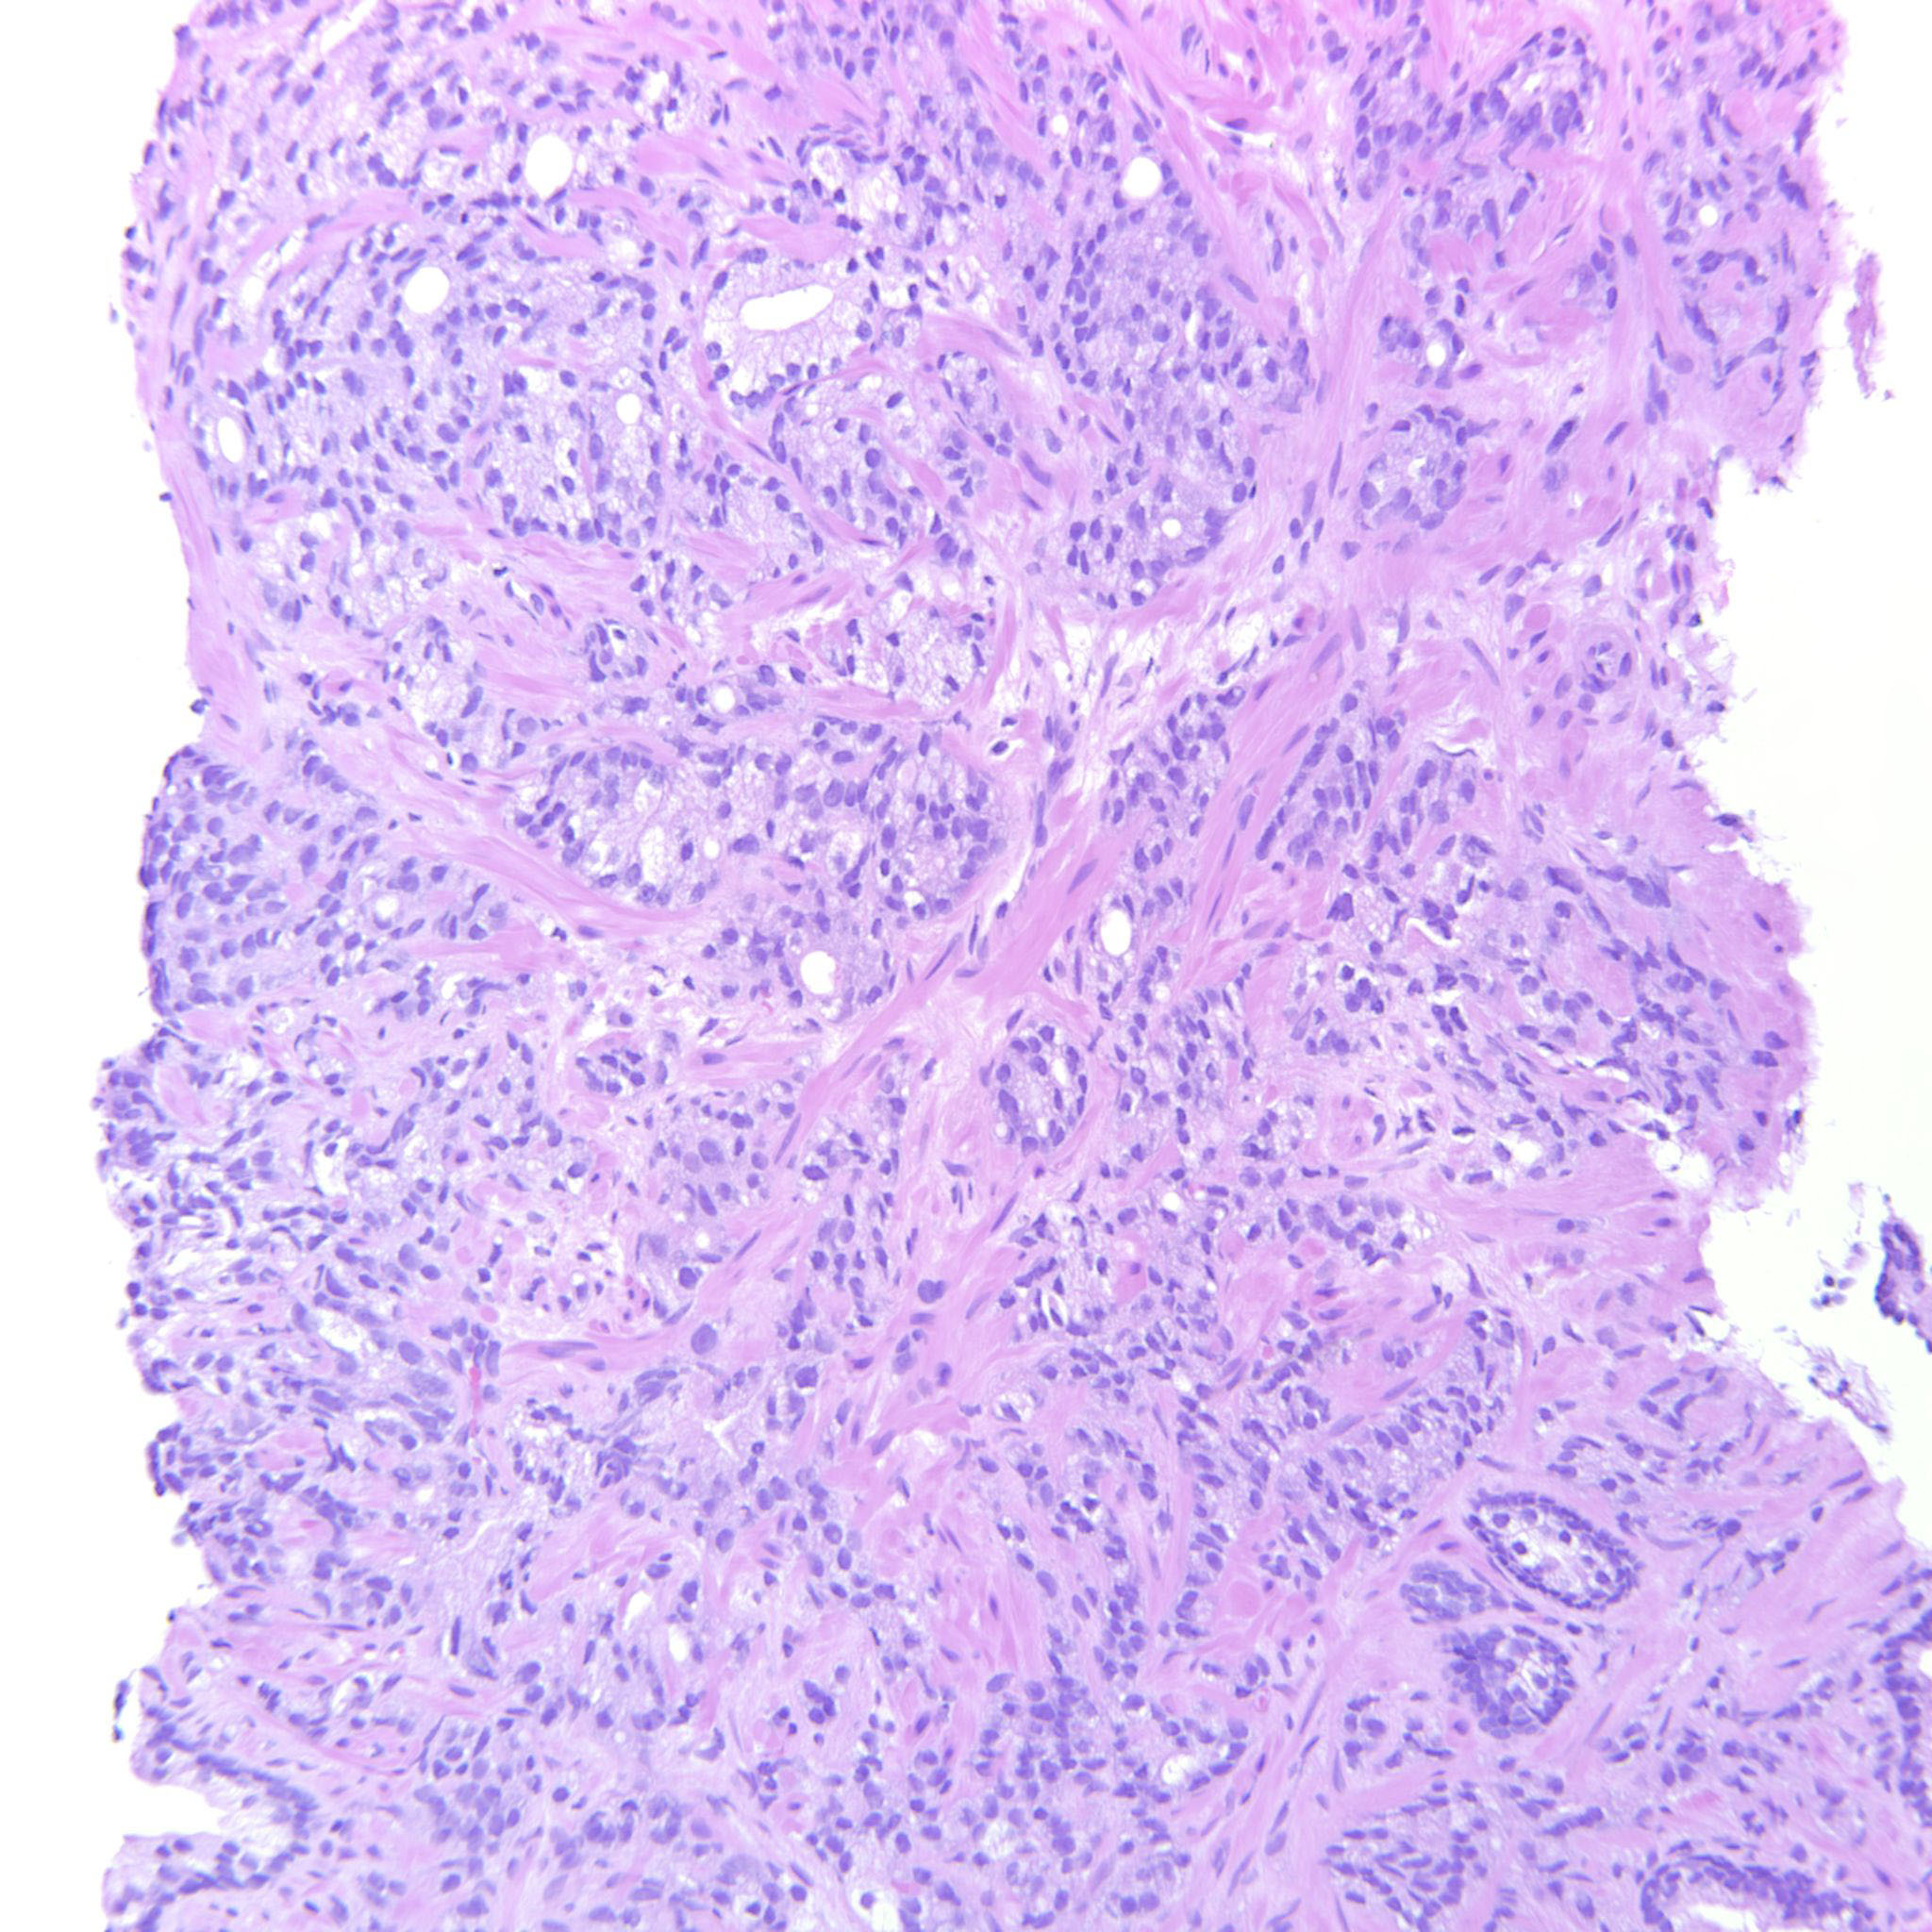

Consensus grade: GS 9-10 (ISUP 5)

Case description (by case creator):

4+5=9 where the GP5 component infiltrates diffusely in strands and single cells.